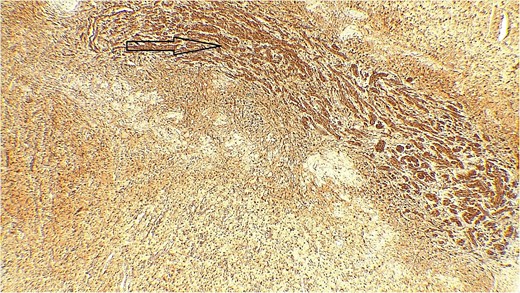

The result of the fine needle aspiration (FNAC) was a bland-looking spindle cell lesion, suggestive of a neural origin lesion like schwannoma. The patient was positioned in a supine position after she received general anesthesia. The face was turned to the opposite side of the tumor with a slight extension of the neck. An S-shaped incision was carried out in the front of the ear to the ear lobule, then it curved around the mastoid process posteriorly near the mastoid process and swung to the upper cervical creases smoothly. The cervical-facial skin flap was elevated with dissection to expose the tumor adequately, and then a traction suture was placed over the earlobe to widen the visual field for the operator. Dissection was carried out until the tumor was completely exposed, showing a smooth, ovoid, and whitish mass along the main trunk of the facial nerve (Fig. 1). The nerve was seen entering and exiting the posterior aspect of the mass on both sides. The layers over the mass were opened, and the mass was enucleated, leaving a flattened nerve posteriorly. No parotid gland excision was carried out. The postoperative histopathological examination revealed neurofibroma (Fig. 2) with a positive expression for S100 immune stain (Fig. 3). Postoperatively, the patient developed moderate (grade III) facial nerve dysfunction with obvious but not disfiguring deformity of the right side of the face, likely due to the pressure effect of the mass or traction during the operation. Two months after the operation, the facial nerve status improved to grade one, and after 4 months, she developed full recovery of facial nerve function.

Immune stain S100, strong nuclear and cytoplasmic staining pattern in the tumor cells.

Surgical management is the mainstay treatment for IGN [19]. This typically involves a partial or total parotidectomy, with careful dissection to preserve the facial nerves and minimize the risk of postoperative complications. In some cases, due to the benign nature of these tumors, a conservative approach may be taken, and regular monitoring is recommended [10]. However, if the tumor causes significant symptoms or there are concerns about malignancy, surgical excision is usually recommended [20]. Furthermore, according to genuine literature, recent advancements in surgical techniques have allowed for more precise and minimally invasive approaches to the resection of these tumors, leading to improved outcomes and facial nerve preservation [21, 22]. Additionally, the use of intraoperative neuromonitoring can play a crucial role in ensuring the preservation of the facial nerve during surgery [23]. Moreover, postoperative follow-up and monitoring are crucial for detecting any signs of recurrence or complications. Immunohistochemistry for S100 staining yields strongly positive results for IGN [10, 24]. In the current case, a total excision of the tumor was done, and the postoperative histopathological examination showed NF with a positive result of the S100 immune stain.